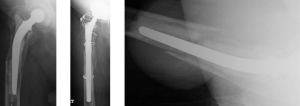

REVISION HIP REPLACEMENT